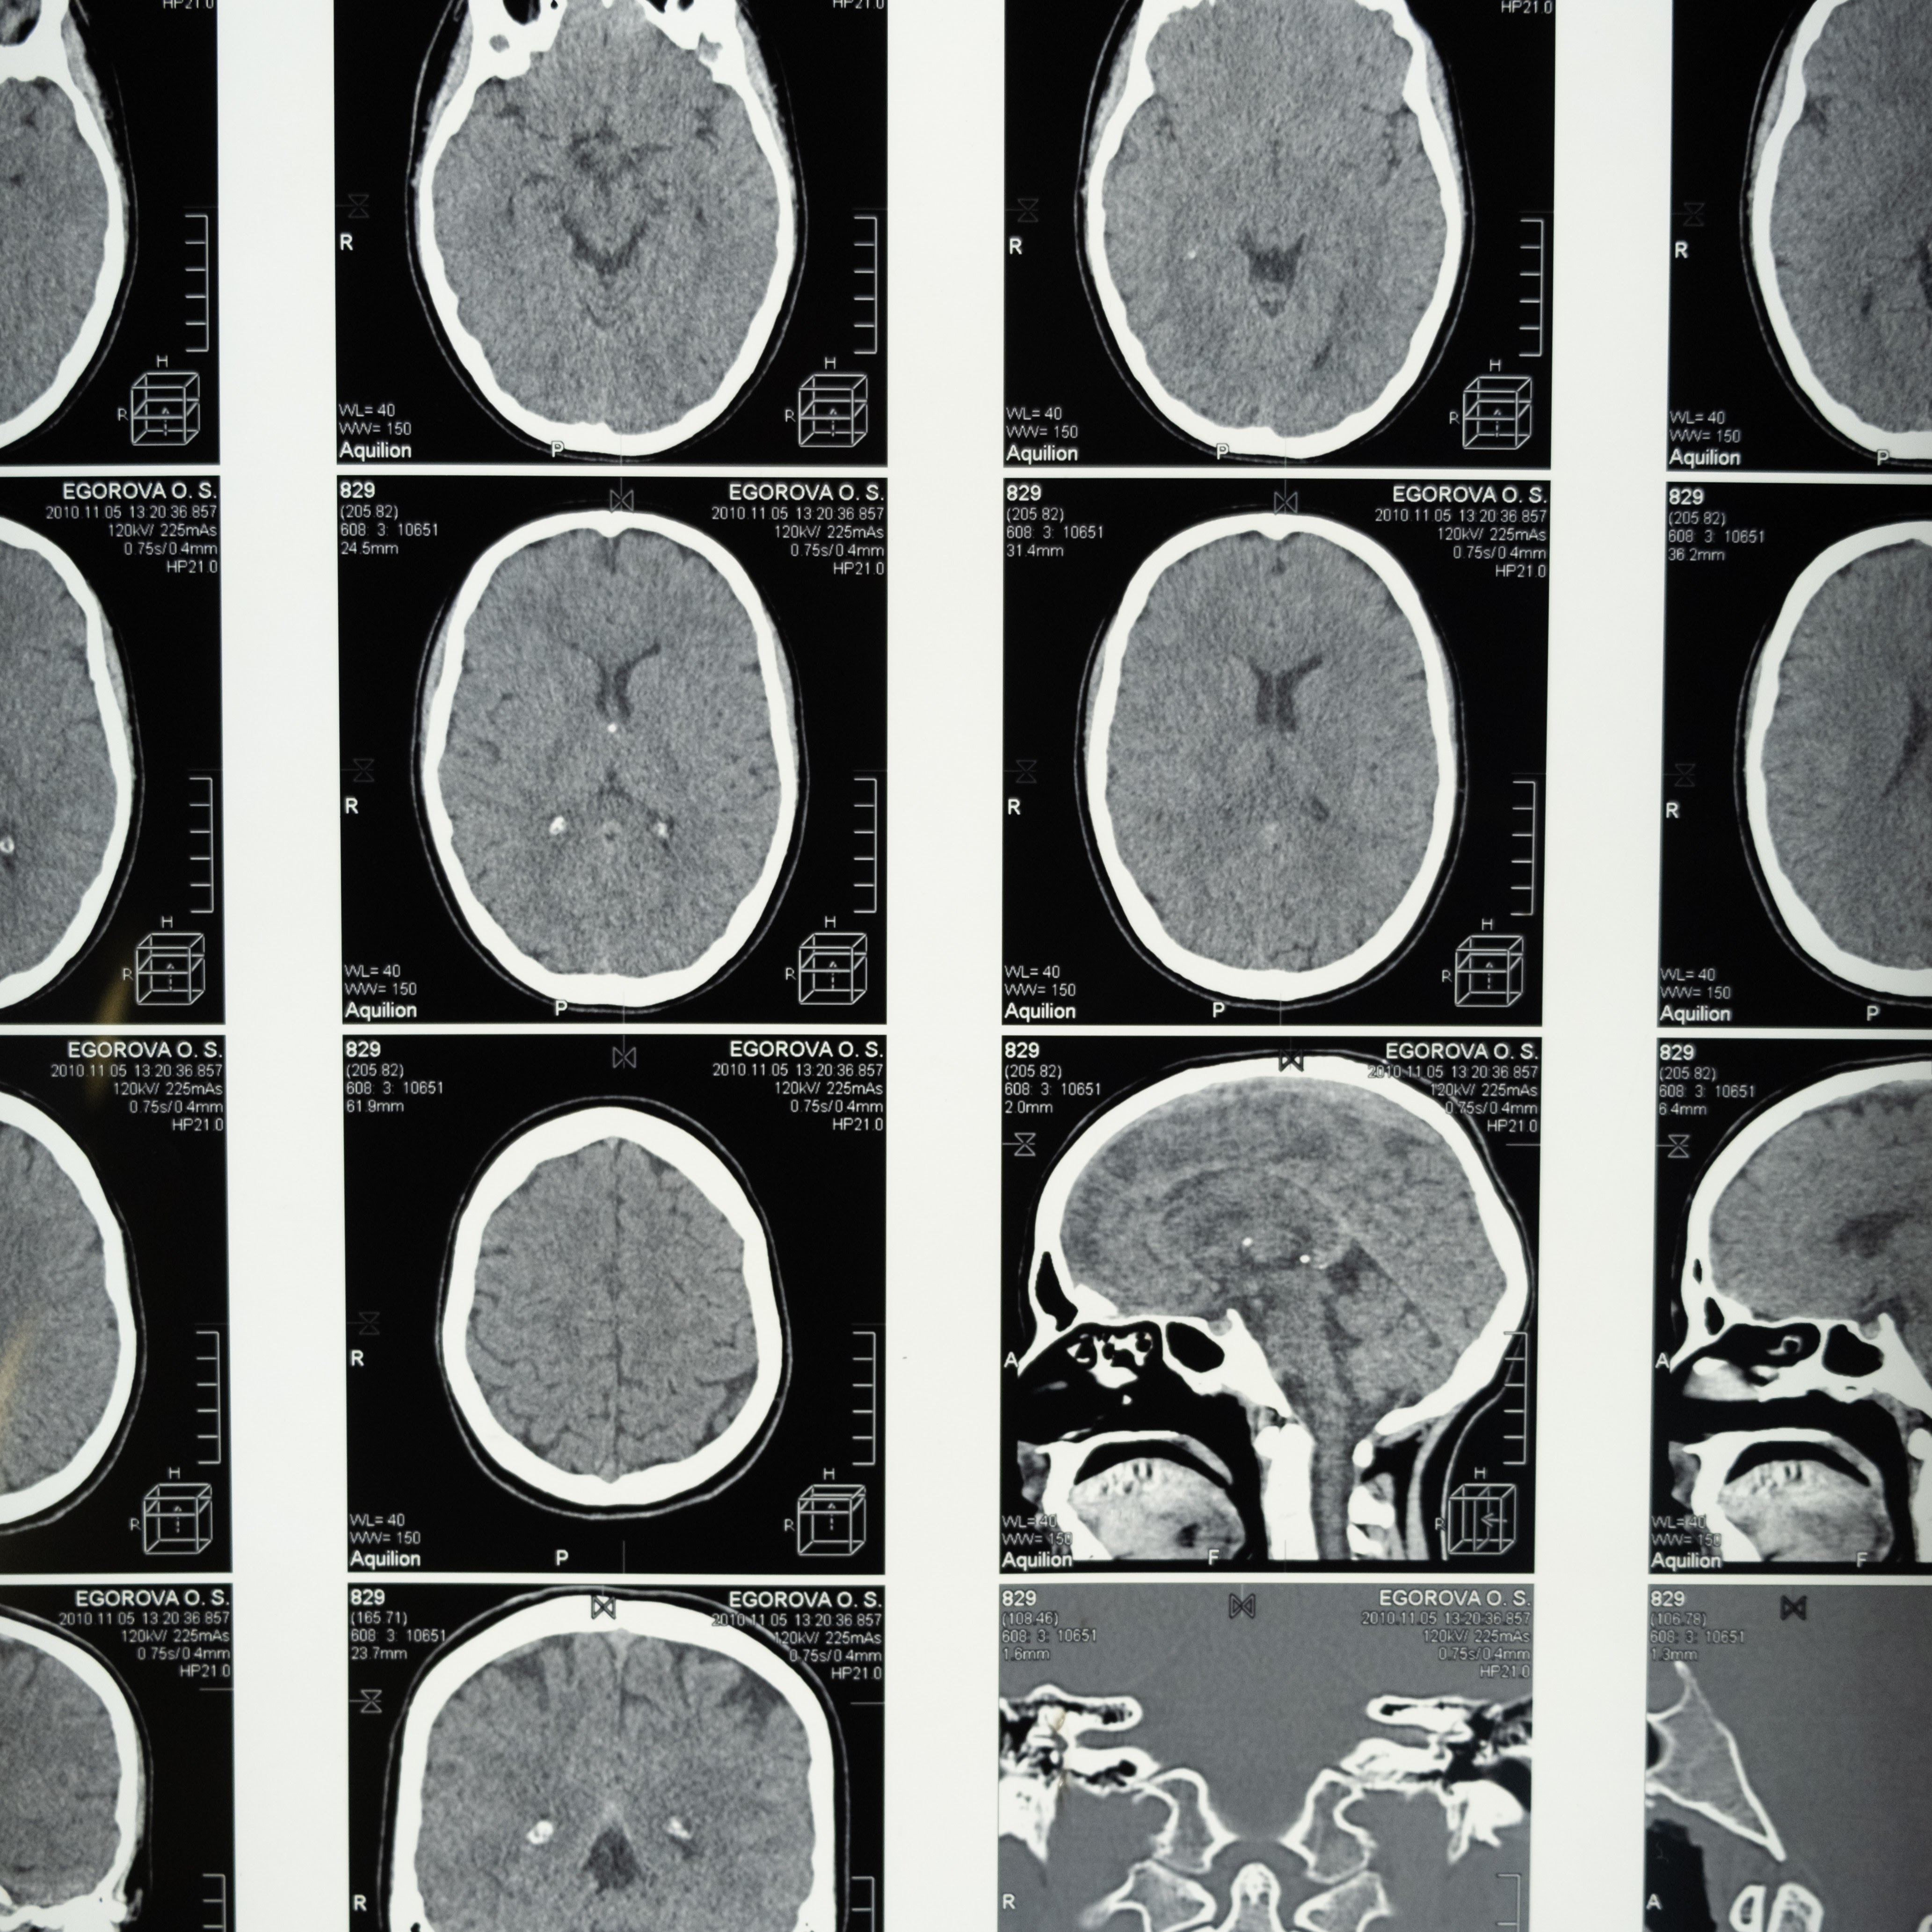

BALANCE is dedicated to building research infrastructure and capacity in collaboration with local and international partners to advance global neurology and health equity research that improves quality of and access to neurological care.